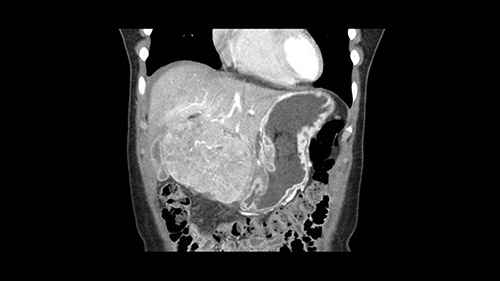

So if we look at the CT scan, on the axial, it’s a larger lesion. It’s about 6 or 7 or 8 centimeters. So it does look a bit threatening in terms of its resectability but if you really drill down deeply into the anatomy, and I think the coronal [imaging] is even better, you can see that the entire mass is on the patient’s left side of the falciform ligament. So it’s really only a left-sided tumor and not even really a left-sided tumor because Segment 4 is uninvolved anatomically.

As I review the CT scan, we have both arterial and venous phases, the tumor is obvious. But I’ll start by saying that the liver itself does not appear to be cirrhotic to my eye. It’s got a normal contour and allied to that, that I do not see evidence of portal hypertension. The spleen is normal, there’s no collateral vessels. The tumor itself, I measured maximally at about 11 centimetres in diameter and I’m told the alpha fetoprotein is very high (over 10000), which is entirely consistent with this being a solitary hepatocellular carcinoma that is very exophytic. It seems to emanate off the inferior margin of Segment 3 (because that’s the falciform). I’ll start by saying that this is not transplantable. The tumor exceeds our guidelines for transplantation, but it's likely resectable based on normal liver and no portal hypertension.

The other thing I would do in this case is to certainly to assess the coronal phase as we can see in the coronal phase, this tumor looks like it's growing from Segment 3, and again I don’t think there’s involvement of the right side of the liver or even on Segment 4.

La decisión aquí, y otra vez mirando, me parce importante mirar a los cortes coronarios porque parece que este tumor cuelga del segmento tres y aquí la cuestión va a ser si vamos a realizar una resección más limitada y hacer una recesión del segmento tres, o si vamos a tener que realizar una hepatectomia izquierda. En cuanto a puntos importantes en ambas opciones, en todos los casos vamos a intentar realizar un recesión anatómica ya que hay datos en la literatura que parecen indicar que una resección anatómica tiene mejores resultados oncológicos comparado con una recesión no anatómica; entonces realizaremos una resección del segmento tres y en este caso trataremos de buscar el pedículo que va al segmento tres, en este caso probablemente sea una resección del segmento tres, realizare una maniobra de Pringle y clampare el hilio para evitar el sangrado.